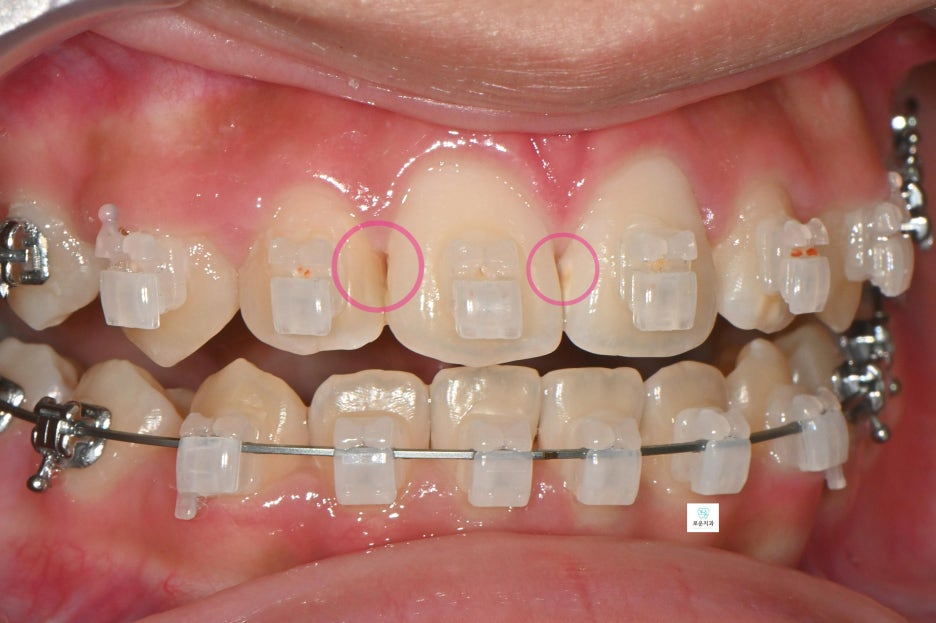

“교정 중 발생한 앞니 사이 충치 치료 사례”

장기간 교정 치료를 진행 중이던 환자분으로

앞니 사이 충치가 발견되어 치료를 위해

내원하셨습니다.

앞니에 생긴 우식은 치아 4개에 사이에 생겨 총 6면의 우식이 발생

→ 치아는 붙어 있는 면 양쪽으로 우식 진행되기 때문에 면수로 진행

엑스레이 촬영 결과

인접면 충치가 더욱 명확하게 확인되었으며

깊이에 따라 마취 후 치료를 진행했습니다.

충치 부위를 제거한 뒤

자연스러운 색상의 레진으로

깔끔하게 수복하였습니다.